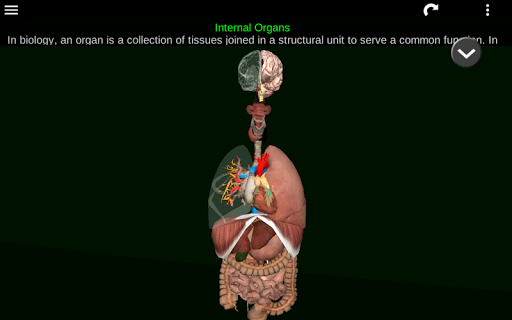

Menampilkan model anatomi 3D dari organ utama tubuh manusia dan penjelasannya masing-masing.

Apa yang ada di aplikasi?

* Sistem pencernaan, termasuk lambung, usus kecil, usus besar, dan animasi sistem ini.

* Sistem pernafasan, yang meliputi trakea, bronkus, paru-paru dan animasi sistem ini.

* Sistem reproduksi, yang meliputi organ reproduksi pria dan wanita.

* Otak, yang meliputi otak, otak kecil, dan batang otak.

* Jantung, yang meliputi atrium, ventrikel, aorta, dan animasi organ ini.

Aplikasi ini dirancang untuk melengkapi studi anatomi dalam berbagai lingkungan pendidikan, kesehatan, dan budaya.

Informasi anatomi yang praktis, berguna, dan berharga di ujung jari Anda.